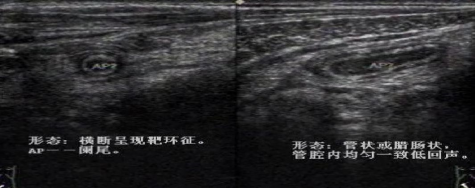

為病變早期,闌尾主要改變是充血、水腫和白細(xì)胞浸潤,炎癥局限于粘膜和粘膜下層,故超聲圖像以粘膜增厚為主,闌尾呈增粗的管狀低回聲盲端結(jié)構(gòu),表面光滑,層次尚清楚,橫斷面呈“靶環(huán)征”,闌尾周圍無或有少量積液。

闌尾顯著腫脹,漿膜高度充血,被纖維蛋白與膿性滲出物覆蓋,或大網(wǎng)膜包裹,闌尾腔內(nèi)積膿,腔壁小膿腫形成。超聲圖:闌尾明顯增粗,外徑>10mm,闌尾壁明顯增厚,呈不均勻低回聲,各層次厚薄不一,壁內(nèi)彩色血流豐富。部分腔內(nèi)可見積液或絮狀沉積物或糞石。腹腔可見渾濁滲出液或膿液。